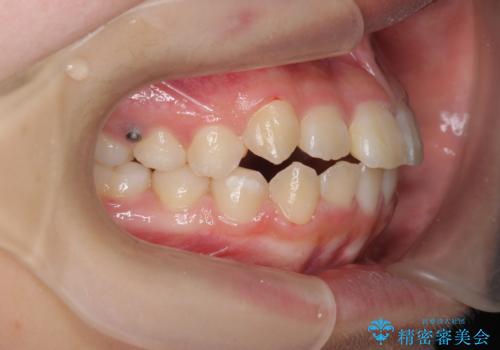

マイクロインプラントを用いた臼歯の後方牽引、およびゴムかけ等の付加処置を駆使して八重歯の治療を行っていきます。

しっかりとゴムかけを頑張っていただいたおかげで、上顎臼歯の後方移動が達成されしっかりとした噛み合わせの構築と、八重歯の治療を達成することができました。